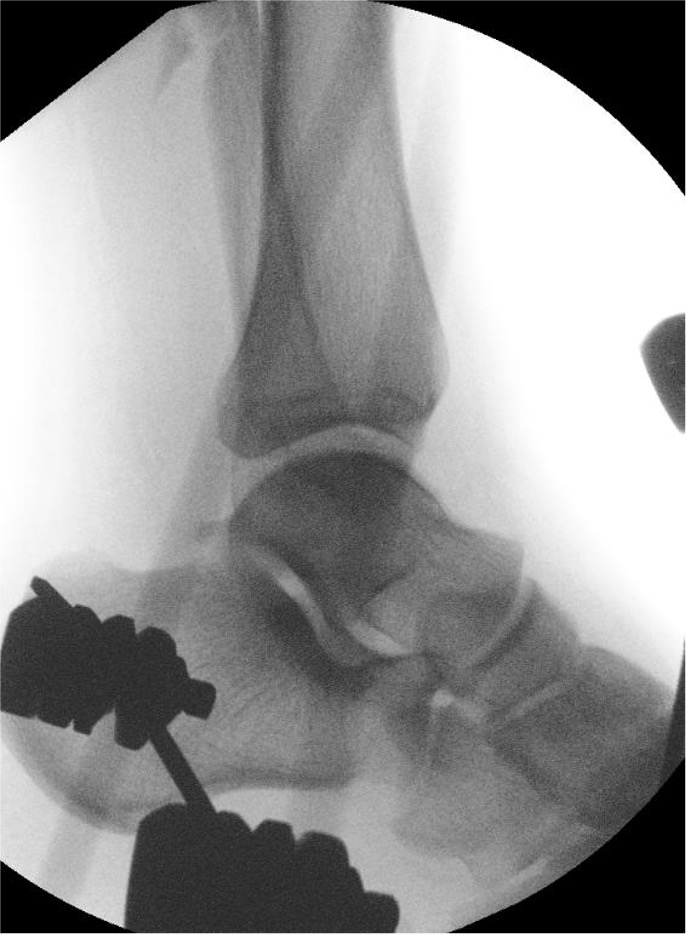

Lateral talar shift / increased medial clear space / deltoid ligament injury

Ankle Fracture Increased Medial Clear SpaceAnkle Fracture Increased Medial Clear Space 2Maisonnerve

Tibia / fibular overlap < 1mm / syndesmotic injury

Ankle Fracture Syndesmosis WidenedAnkle Diastasis